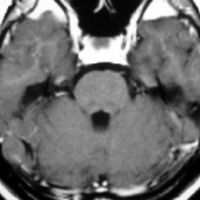

海綿状血管腫 微小血管障害

- 放射線治療を受けた患者の40%くらいで,微小出血/海綿状血管腫が発生します

- 照射後10年くらい長期観察をしていると実際に非常に高頻度にみます

- 海綿状血管腫は,放射線誘発2次腫瘍というよりも,放射線による脳内小血管損傷による血管障害として捉えた方がよいです

- T2スターというMRI画像で発見できます

- 低信号(黒いシミみたいなもの)として脳内たくさん見られることがあります

- これは血液の中の鉄分が脳に滲み込んだ形跡をみているものです

- だから,海綿状血管腫とは言わないで,微小出血 microbleeds, blood leak(血液が漏れた痕跡)と読んだ方がいいものです

- 海綿状血管腫というと腫瘍みたいだからです

- 年月の経過とともに数が増加します

- 海綿状血管腫は発生しても何ら症状を呈することはありません

- 治療をせずに放置します

- まれに小さな脳出血を生じますが,経過を見れば血腫は自然に吸収されます

- またサイズが大きな皮質を侵す海綿状血管腫は症候性てんかんを生じることがあります

- とても大きなもの2から3cm以上くらいになると摘出を考えることもあります

- でもほとんど手術などしないでほっておきます

4歳の時に低線量頭蓋照射を受けていますが,医療関係の仕事について自立していた33歳の女性です。仕事中に記憶が飛ぶという症状がでて,周囲からおかしいと言われて受診しました。右の扁桃体のところ(左側のMRI)に海綿状血管腫ができていて,側頭葉てんかん(欠伸発作)を生じていました。バルプロ酸の投与で発作は止まって職場復帰しています。